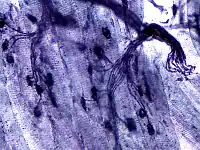

![]() Junção neuromuscular A: axônio do motoneurônio; B: terminal do axônio; C: fenda sináptica; D: fibra muscular; E: parte de uma miofibrila. O processo ocorre nos seguintes passos: 1. Chegada do potencial de ação ao terminal axonal; 2. Abertura de canais de cálcio voltagem-dependentes e entrada do cátion na célula; 3. Exocitose dos neurotransmissores de acetilcolina pela fusão entre as membranas do motoneurônio com as das vesículas sinápticas; 4. Interação da ACh com seu receptor no sarcolema; 5. Entrada de sódio na fibra muscular; 6. Geração de potencial de ação, que vai até as miofibrilas, pela entrada de sódio e saída de potássio. |